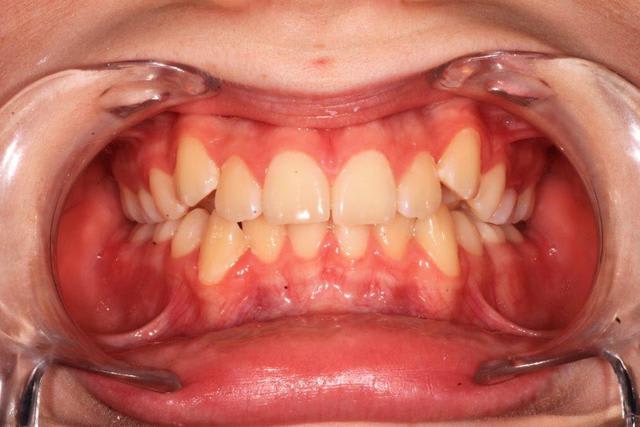

Il faudrait plus d'éléments pour répondre ( télé profil, pano, photos endo et exo buccales)

quelques documents :